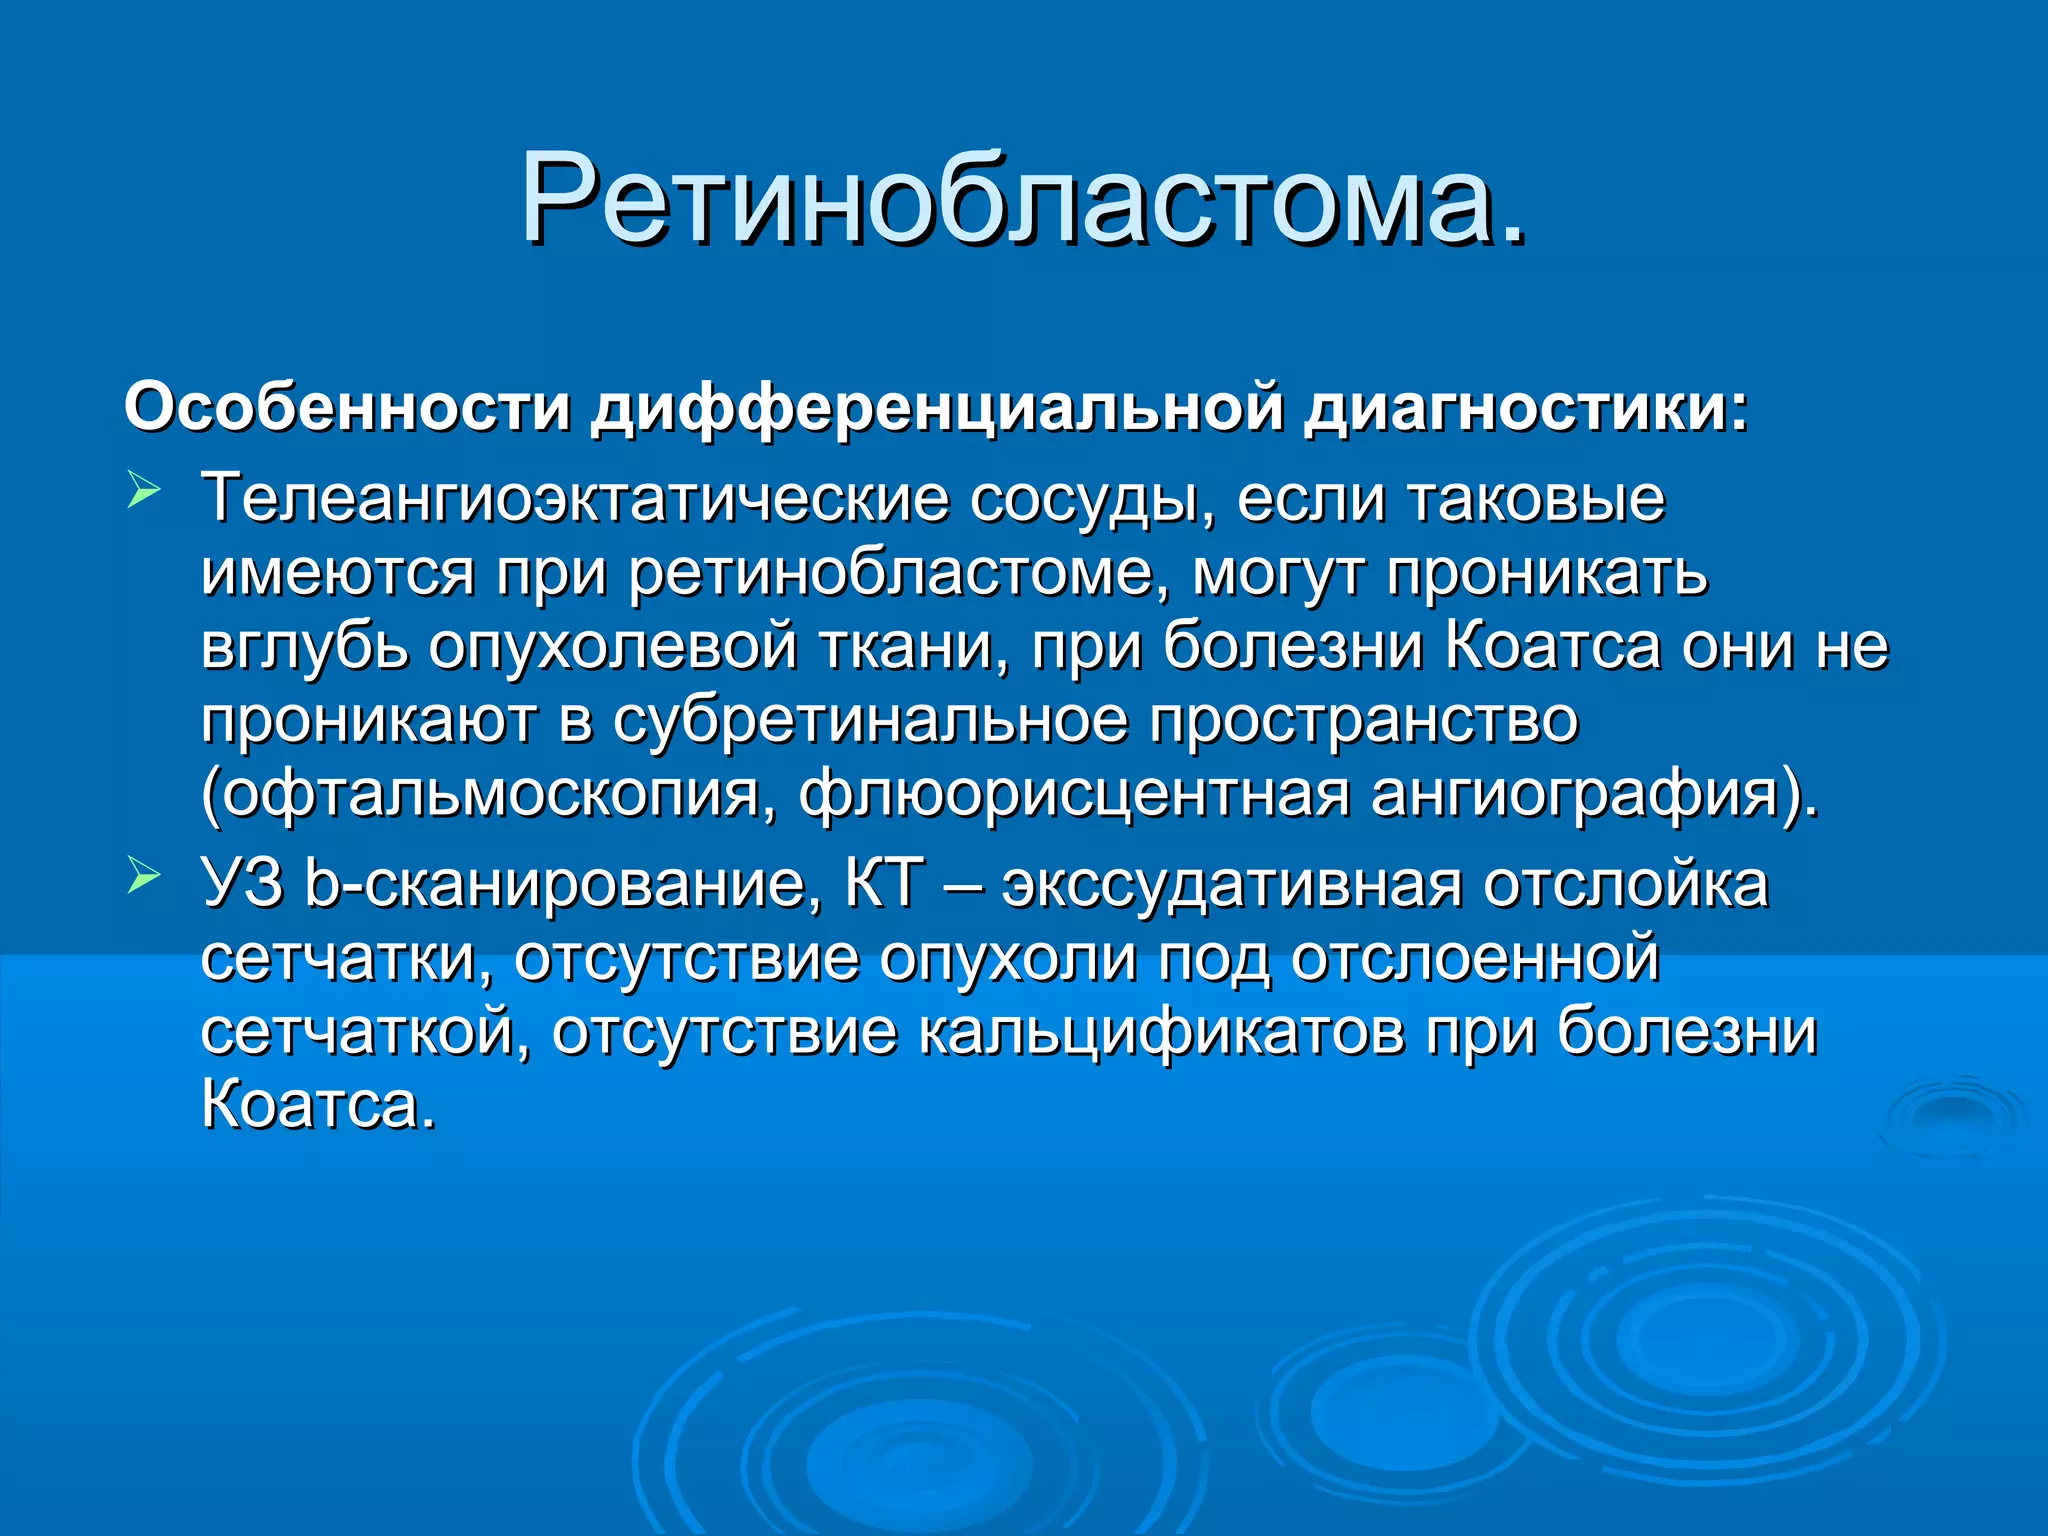

Болезнь Коатса - это идеопатическое заболевание, характеризующееся полиморфными изменениями сосудов сетчатки с массивной экссудацией, чаще всего у детей и подростков, с преобладанием среди мальчиков. Эпидемиология показывает, что заболевание проявляется, как правило, в возрасте 8-16 лет, но возможно его обнаружение и у взрослых. Основные проявления включают ретинальные аномалии, субретинальную экссудацию и постепенно прогрессирующую потерю зрения.